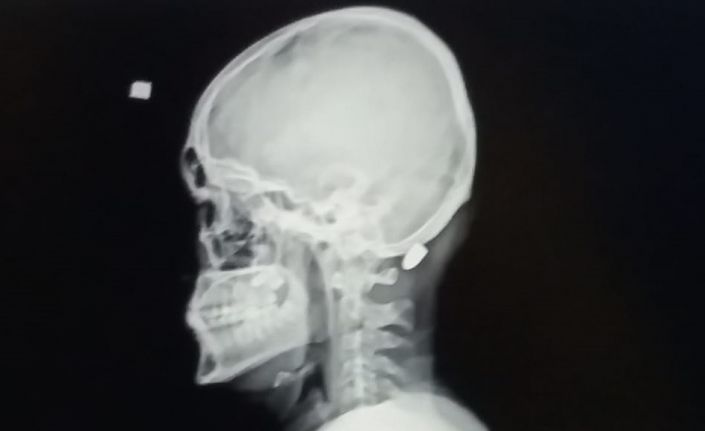

Trabzon’un Vakfıkebir ilçesindeki Karadağ Yaylası’nda bir evin dış cephe kaplamasını yapan 18 yaşındaki Ali Kuleyin’in başına nerden atıldığı belli olmayan kurşun isabet etmiş, ilk önce kurşun olduğunu anlamayan genç, elini başına götürdüğünde kan geldiğini anlayınca hastaneye kaldırılmıştı. İsabet eden yorgun mermi başarılı bir operasyonla saplandığı yerden çıkartılmıştı.